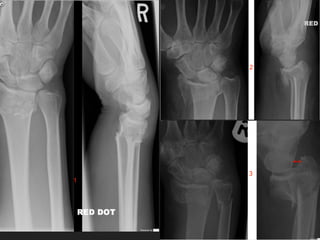

FIND THE FRACTURE

WAS IT DIFFICULT?

▸ HOW COMMON IS IT?

▸ HOW SEVERE IS IT?

FIND THE #

▸ HOW COMMON IS IT

▸ HOW SEVERE IS IT

WHAT IS IT CALLED?

▸ WHAT IS THE DANGER OF THIS #

▸ THESE FRACTURES CAN BE

SUBTLE

▸ CHECK FOR PAIN IN THE

ANATOMICAL SNUFFBOX

▸ IF YOU ARE UNSURE THEN

BETTER TO PUT IN A POP AND RE

X-RAY IN 10-14 DAYS